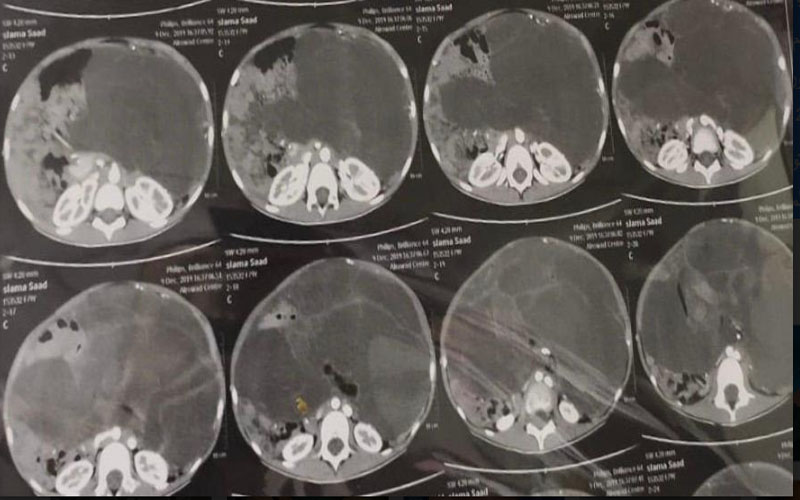

ومن جانبه أوضح الدكتور ماهر مختار مدير مستشفى الأطفال الجامعي بأسيوط أن أهل الطفلة لاحظوا وجود انتفاخ بشكل غير طبيعي في البطن، ما استدعى توجههم لمحافظة أسيوط لفحص الحالة بمعرفة أحد الأساتذة المتخصصين، وهو ما قام به الدكتور محمد مدحت نصر مدرس الجهاز الهضمي الذي أجرى عددًا من الفحوصات التي أثبتت وجود ورم ضخم في بطن الطفلة يستدعي استئصاله.

وأضاف الدكتور طارق صبرة مدرس واستشاري الجراحة العامة وجراحة الأطفال أن حالة الطفلة كانت تستدعي جراحة دقيقة لاستئصال الورم بشكل كامل والذي كان يشمل معظم محيط البطن وناشئ من المبيض الأيسر وهو ما تم شرحه لأسرة الطفلة للموافقة على إجراء العملية حيث تم تشكيل فريق طبي تحت رعاية الدكتور إبراهيم علي رئيس وحدة جراحة الأطفال بالمستشفى وبرئاسة الدكتور طارق صبرة، ويضم الدكتور حسين إبراهيم فرح المدرس المساعد بقسم جراحة الأطفال والطبيب أحمد كامل الطبيب المقيم بالقسم إلى جانب فريق التخدير والذي يضم الدكتورة سهام معين الأستاذة المساعدة بقسم التخدير والدكتور أيمن عبد الخالق المدرس بالقسم والطبيب محمد سالم حيث نجح الفريق الطبي في استئصال الورم بالكامل في جراحة استغرقت ثلاث ساعات مع المحافظة على المبيض والأنبوبة الرحمية وتعافي الطفلة بشكل كامل.